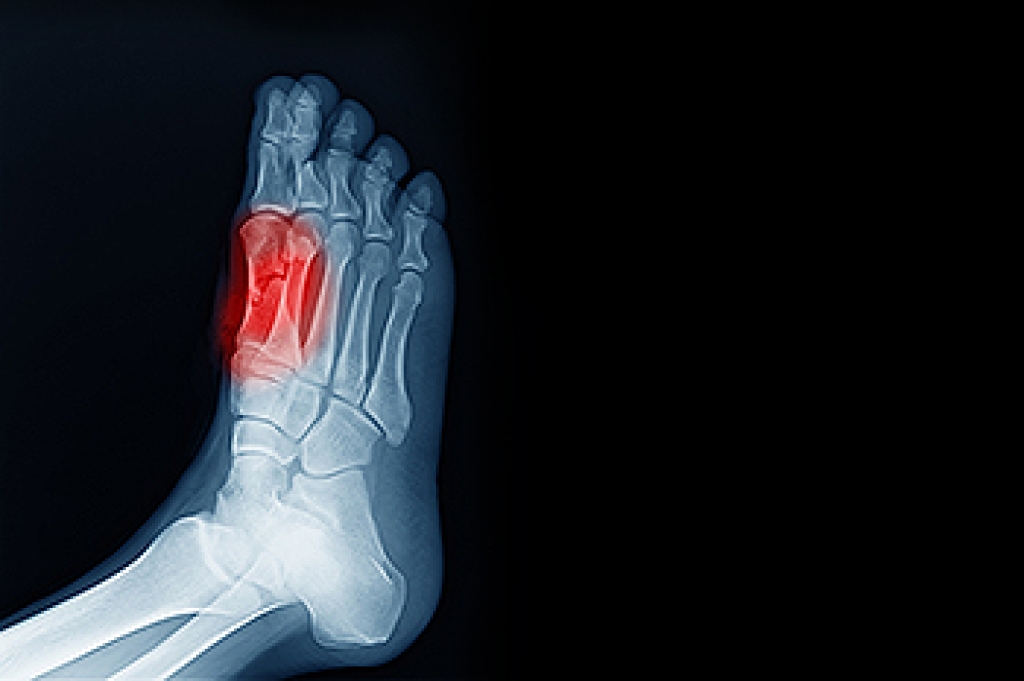

Gout is a type of arthritis caused by a buildup of uric acid crystals in the joints, often affecting the big toe, but also the foot and ankle. Symptoms include sudden, severe pain, redness, swelling, and warmth in the affected joint, making walking or standing difficult. Risk factors include a diet high in purines, obesity, genetics, alcohol consumption, and certain medical conditions. Repeated gout attacks can lead to joint damage, decreased mobility, and long-term discomfort. A podiatrist can diagnose gout, recommend lifestyle adjustments, prescribe medication, and provide care to reduce pain and prevent future attacks. Early intervention helps protect joint health and improve mobility. If you have gout symptoms in your big toe or foot, it is suggested that you promptly consult a podiatrist who can help you to manage this painful condition.

Gout is a type of arthritis caused by a buildup of uric acid in the bloodstream. It often develops in the foot, especially the big toe area, although it can manifest in other parts of the body as well. Gout can make walking and standing very painful and is especially common in diabetics and the obese.

Gout can easily be identified by redness and inflammation of the big toe and the surrounding areas of the foot. Other symptoms include extreme fatigue, joint pain, and running high fevers. Sometimes corticosteroid drugs can be prescribed to treat gout, but the best way to combat this disease is to get more exercise and eat a better diet.